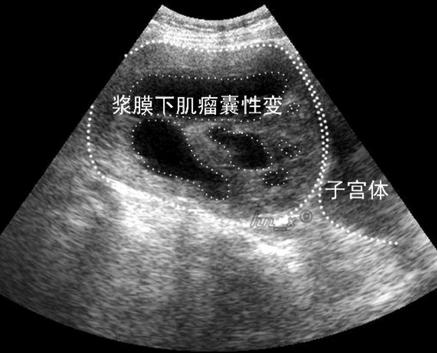

子宫肌瘤玻璃样变图片

子宫肌瘤玻璃样变图片,子宫肌瘤肉瘤样变图片

子宫肌瘤变性一例

请大家欣赏,子宫肌瘤玻璃样变

子宫肌瘤囊性变图片

浆膜下子宫肌瘤图片